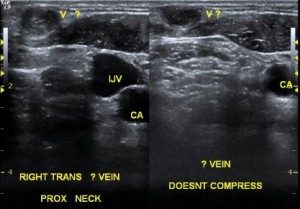

Jugular vein thrombosis is not common. It may occur in the internal or in the external jugular vein. Usually, a clot in the internal jugular vein is either the result of a procedure, or extension of clots in the arm veins.

External jugular vein thrombosis

In contrast to a clot in the internal jugular vein, there is even less information about external jugular vein thrombosis. These are superficial vein thrombi. Probably, they also occur most commonly in relation to neck catheter insertion. Clinically, a patient will complain of a swollen, painful, elongated mass on the neck. Sometimes there is inflammation. Then it is thrombophlebitis. Importantly, clots in the external jugular vein can propagate to the internal jugular veins.